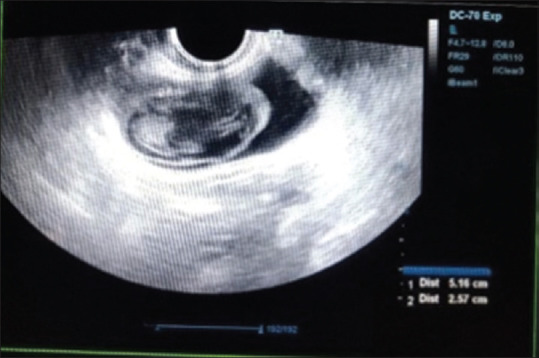

Owing to its simplicity, transvaginal oocyte retrieval (TVOR) has become the standard procedure for oocyte retrieval. Despite being an easy procedure, TVOR is still associated with rare but serious complications. A high index of suspicion is required for early diagnosis of complications. We present two cases of bladder haematoma, which presented to us post-TVOR.